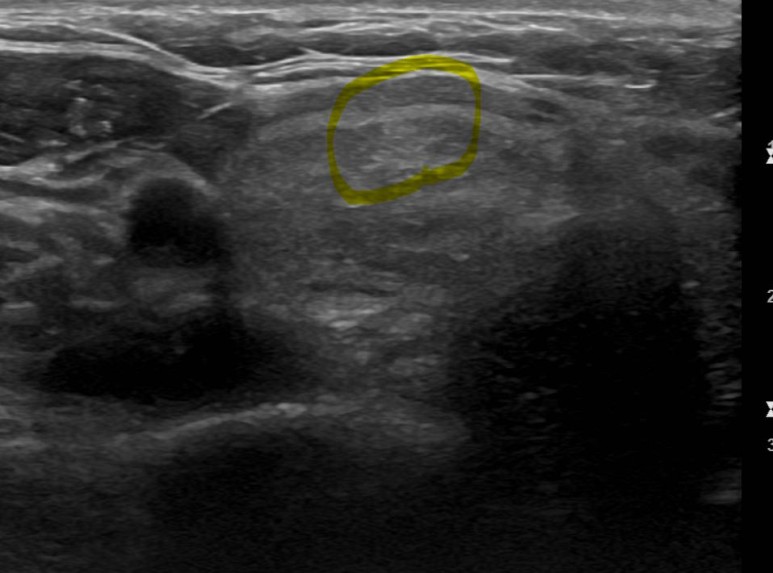

본원에서 갑상선세침흡인세포검사로 진단받은 갑상선암의 증례가 간혹 이어지는 목 이물감으로 인해 본원에 내원하신 30대 남성이었습니다.갑상선 초음파를 저희 병원에서 시행하였습니다.

갑상선의 좌우로 연결하는 잘록한 부위에 1.3센티미터 정도의 결절이 관찰되었습니다. 결절 내부에 석회 부분도 함께 세침 흡인 세포 검사를 실시했습니다.